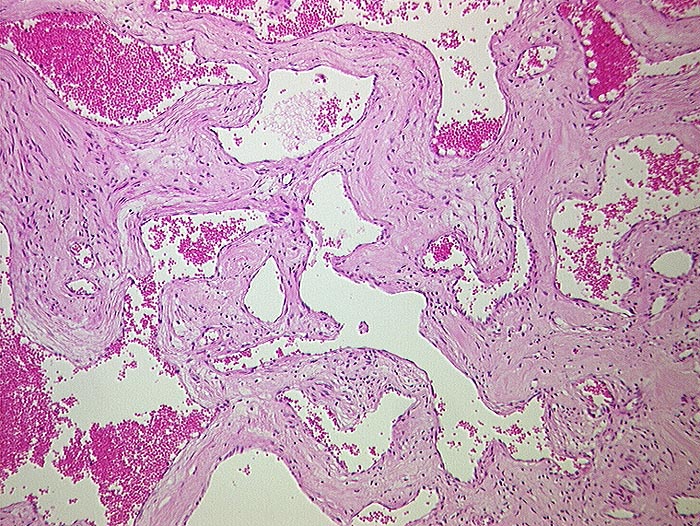

Hämangiom

benigner Tumor

Leber

Makroskopie

Befund

Pathologischer Befund